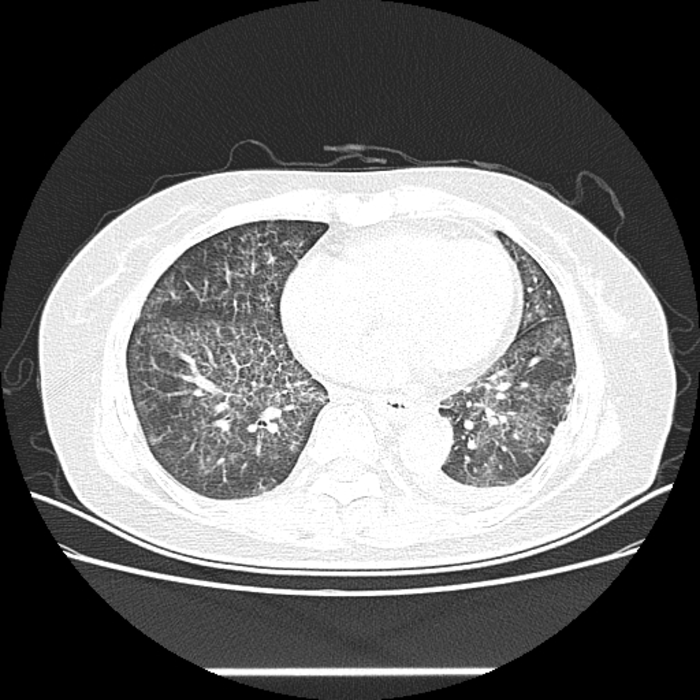

患者,女,63岁,因“发热伴呼吸困难5天”入院。

辅助检查:血常规、降钙素原未见异常。胸部CT示:两肺弥漫网格状磨玻璃密度影,小叶间隔增厚,呈铺路石样改变。

图10

这是什么病呢?病毒感染还是特殊病原体感染或是非感染性疾病?

为了进一步明确,我们行支气管镜检查,在镜下行支气管肺泡灌洗等,并留取标本检查。

图11

灌洗液呈乳白色(放置后乳白色沉淀),过碘酸雪夫染色(PAS)阳性。冷冻活检病理考虑:肺泡蛋白沉积症(PAP)。

肺泡蛋白沉积症是一种“无药可治”的疾病,更准确地说,肺泡蛋白沉积症的主要治疗方法不是药物,而是予支气管镜下全肺肺泡灌洗。

这个病例告诉我们,不明原因的发热或难以明确胸部异常影像的病因时,支气管镜检查是攻克难题的重要“利器”,有些时候不但是诊断的重要手段,也是治疗的唯一手段。